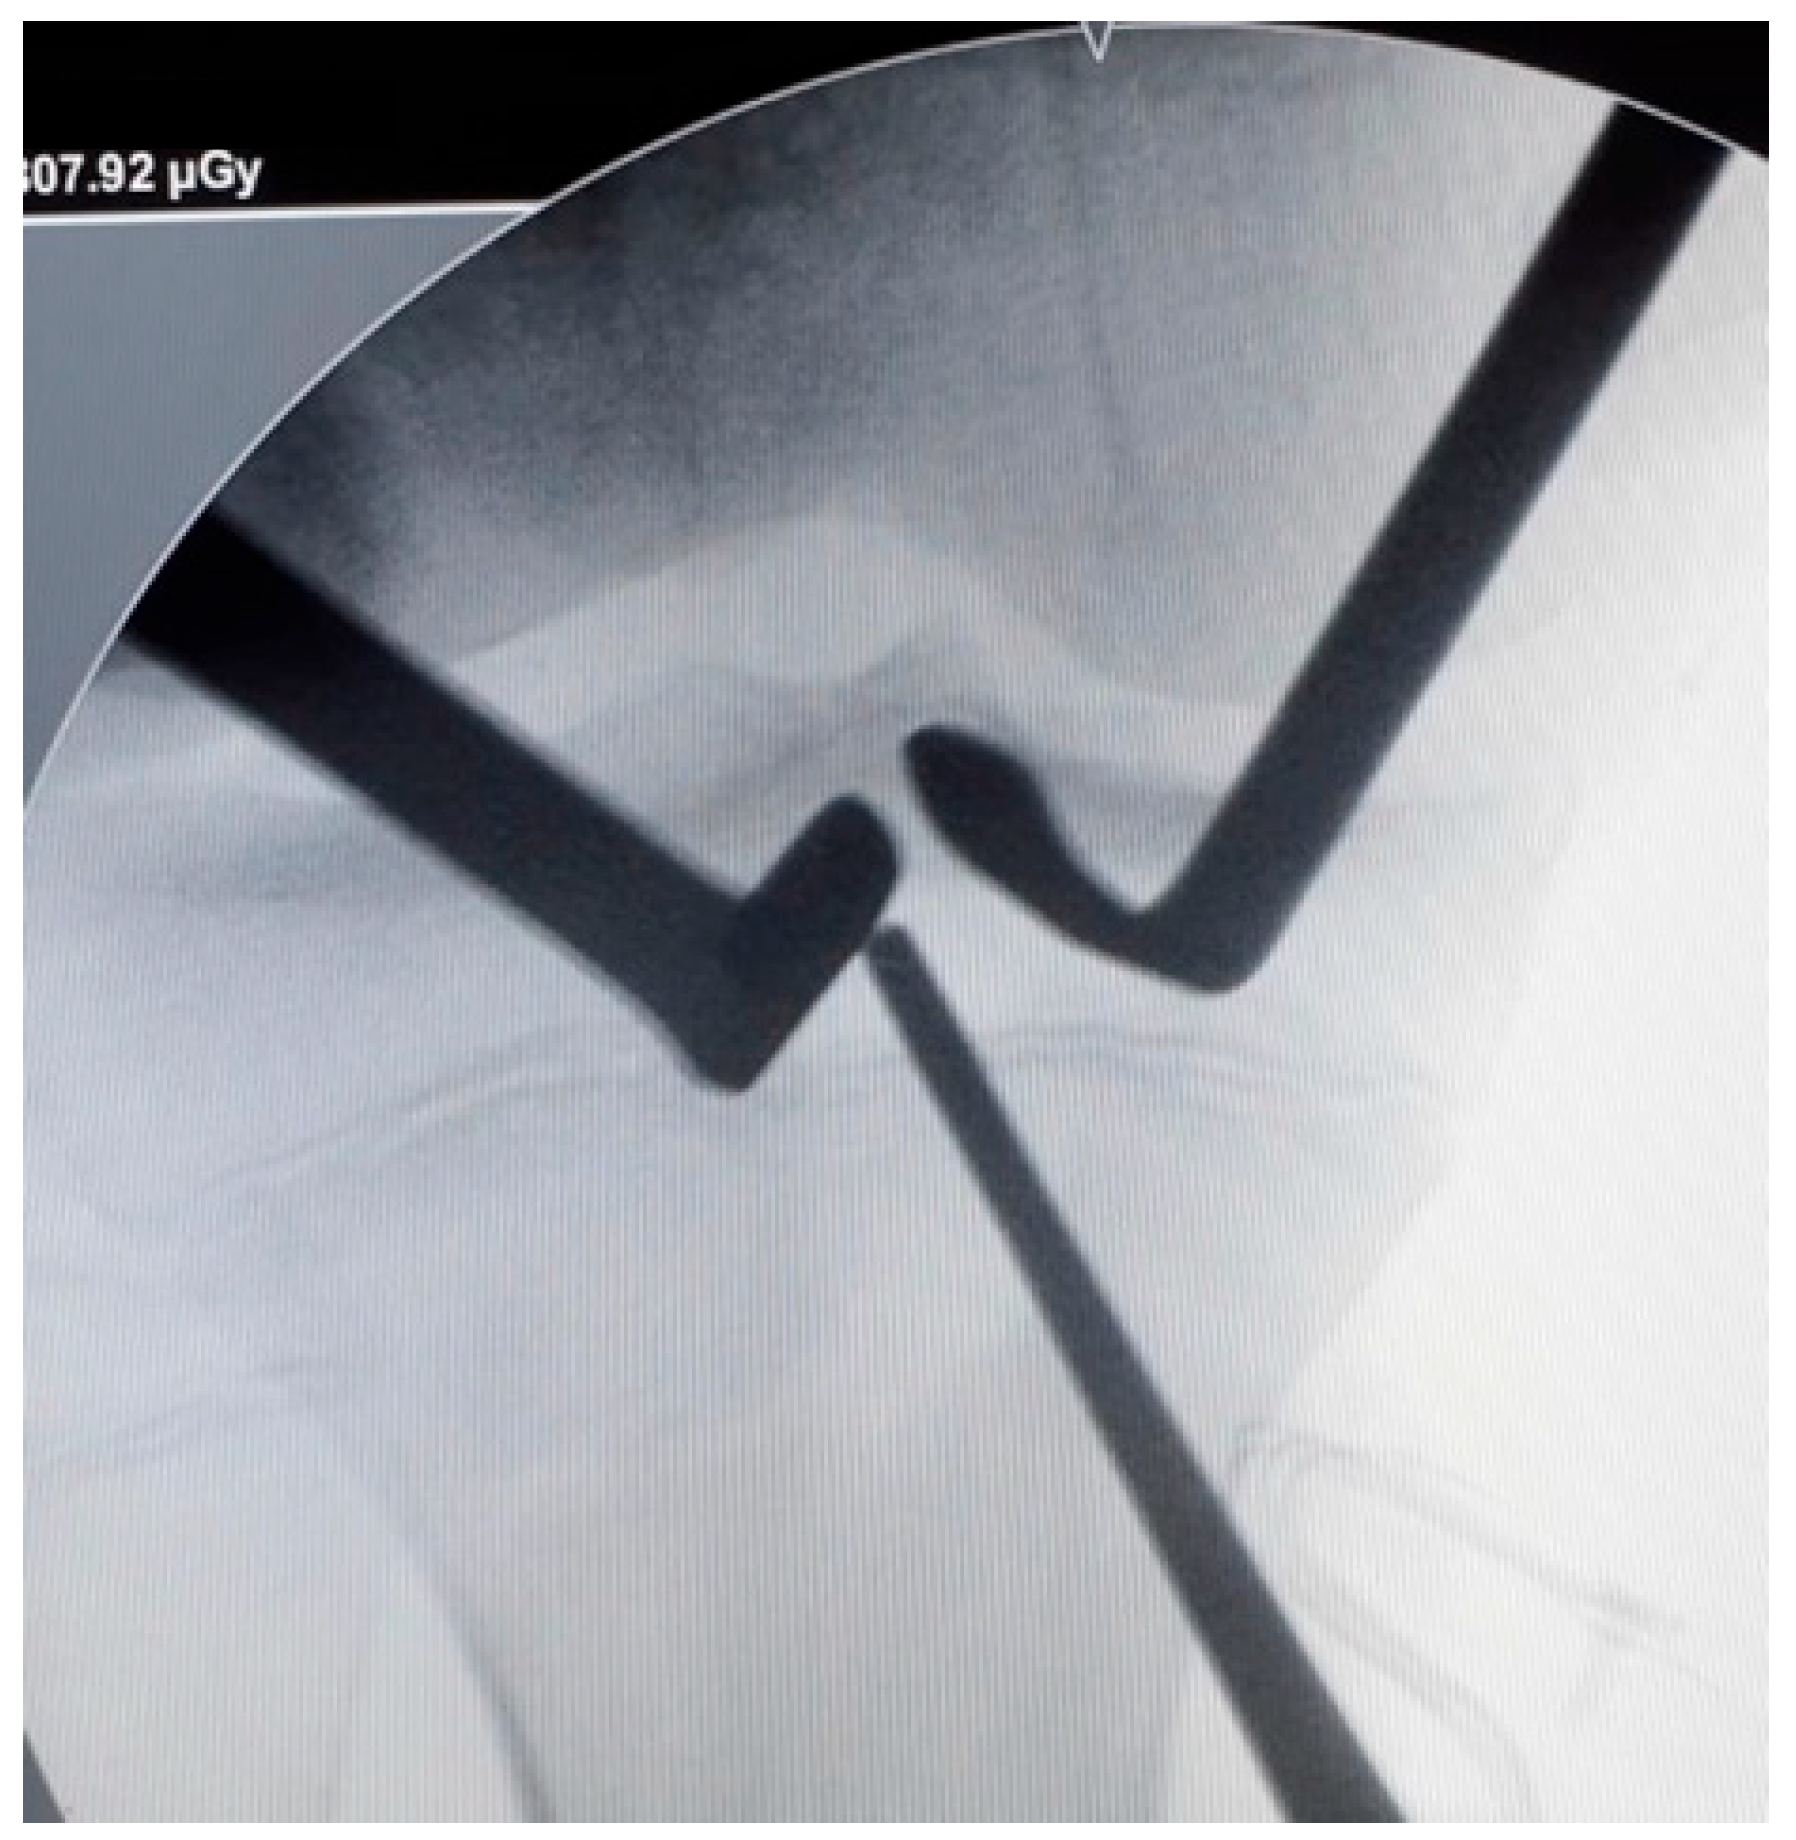

2.2. Surgical Technique

- Gómez Cáceres, A.; Mariño, I.T.; Martínez Malo, F.J.; Vieitez Riestra, I.; Idiart, R.P. “Over-the-Top” Anterior Cruciate Ligament Reconstruction Associated With a Lateral Extra-Articular Tenodesis in Children. Arthrosc. Tech. 2023, 12, e441–e448. [Google Scholar] [CrossRef]